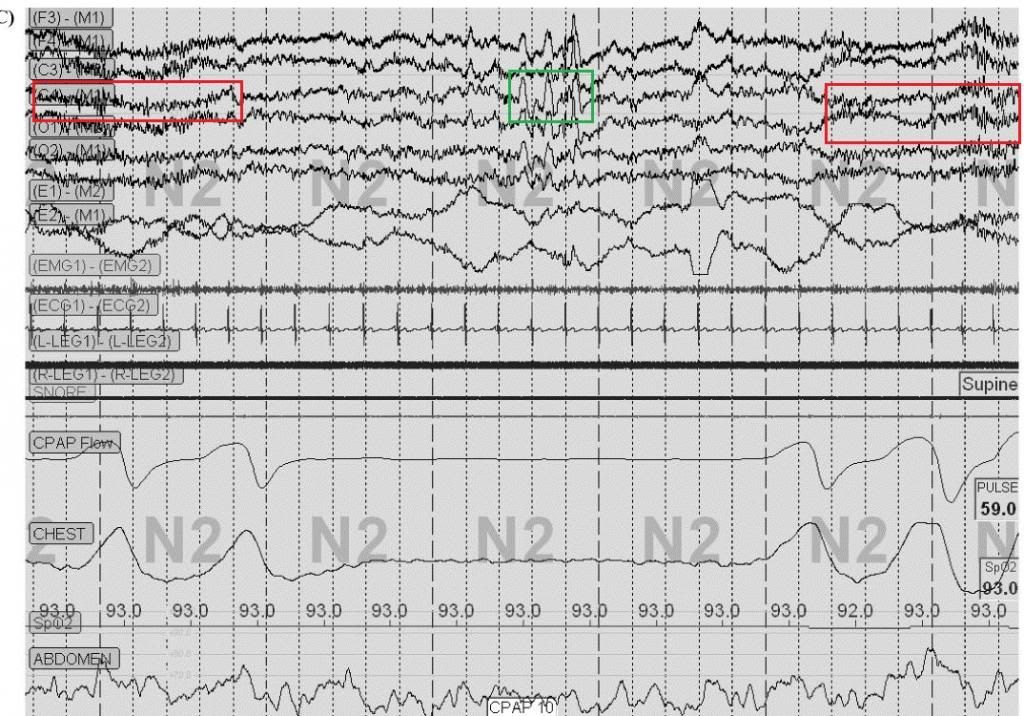

Unfortunately, it isn't "ballistocardiographic effect" this time, as much of the "expiratory intolerance" appears to be related to body motion (see movement in chin and leg leads):mollete wrote:Presently, his scheme is to use ASV. He's still touting "Expiratory Intolerance", but sheepishly says "Yeah, well could be ballistocardiographic effect", a concept he was also introduced to here.

Further, that really doesn't look a lot like REM ("R"), looks more like NREM2. Or else that chin movement makes this REM Behavior Disorder. Chest belt inverted (backwards). Abdominal belt looks blown.